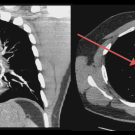

A 34-year-old man presented to the emergency department with a nonproductive cough and progressive dyspnea on exertion over the course of a week.